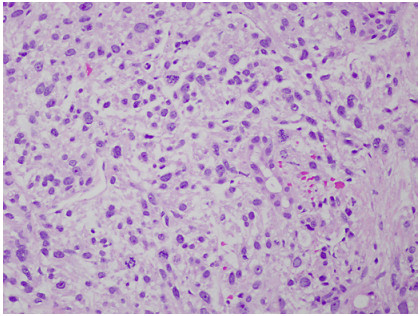

Abstract: Leiomyosarcomas (LMSs) are extremely rare and comprise only 1.2% of small bowel malignancies. Advancements in immunohistochemical techniques have allowed for the differentiation between LMSs and gastrointestinal stromal tumors. LMSs remain difficult to detect via endoscopy and require a more intricate diagnostic approach. The staging and sizing of these tumors are important prognostic indicators. We report a case of a 67-year-old male who presented with bulging lower extremity veins, abdominal bloating, and weight loss. A CT of the abdomen and pelvis revealed a pelvic mass arising from the small bowel and a metastatic hepatic lesion, which was found to be compressing the inferior vena cava. A biopsy of the hepatic lesion confirmed the diagnosis of metastatic LMS.